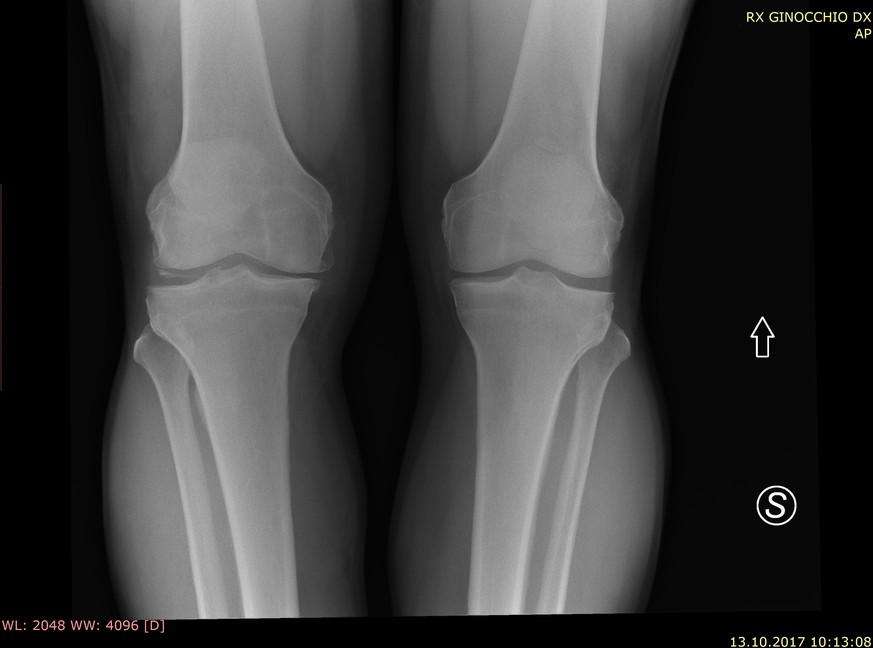

Auf die Unterlagen - etwa Brustkrebsscreenings, Wirbelsäulenbilder, Röntgenaufnahmen eines Brustkorbs oder Herzschrittmacher - hätte jeder zugreifen können, wie der Bayerische Rundfunk (BR) am Dienstag nach Recherchen des Senders mit der US-Investigativplattform ProPublica berichtete. In der Schweiz sind laut einem Bericht der Greenbone Networks GmbH zwei Systeme mit 1500 Datensätzen von Patientinnen und Patienten und insgesamt 197'000 Bilder betroffen.

Die Bilder seien hochauflösend und mit vielen Informationen versehen, fast alle davon personenbezogen: Geburtsdatum, Vor- und Nachname, Termin der Untersuchung und Informationen über den behandelnden Arzt oder die Behandlung selbst.